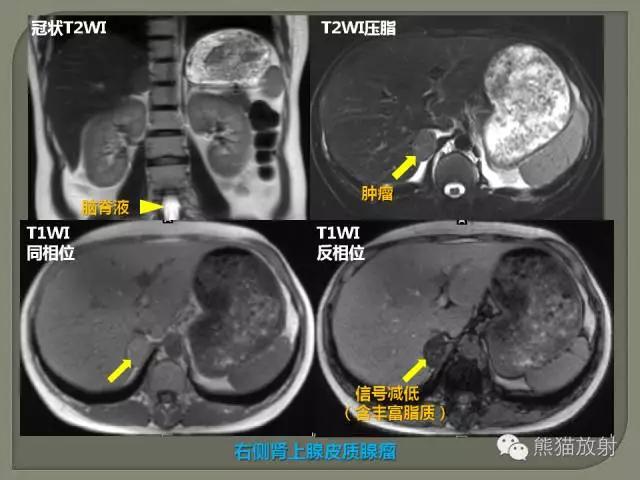

3、水为长T1长T2,脂肪为短T1长T2。

4、长T1为低信号(暗),短T1为高信号(亮)。

5、长T2为高信号(亮),短T2为低信号(暗)。

7、脂肪T1白,T2灰白。

T1加权像 短TR、短TE——T1加权像,T1像特点:组织的T1越短,恢复越快,信号就越强;组织的T1越长,恢复越慢,信号就越弱。

T2加权像 长TR、长TE——T2加权像, T2像特点:组织的T2越长,恢复越慢,信号就越强;组织的T2越短,恢复越快,信号就越弱。

脂肪、骨髓不论在T1WI、T2WI和PDWI(质子加权像)图像上均呈高信号